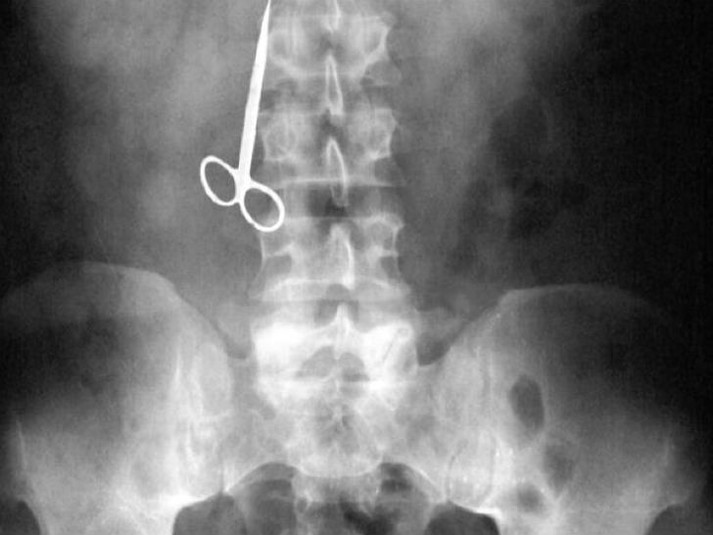

Вот буквально несколько примеров тех вещей, которые были обнаружены в человеческом желудке.